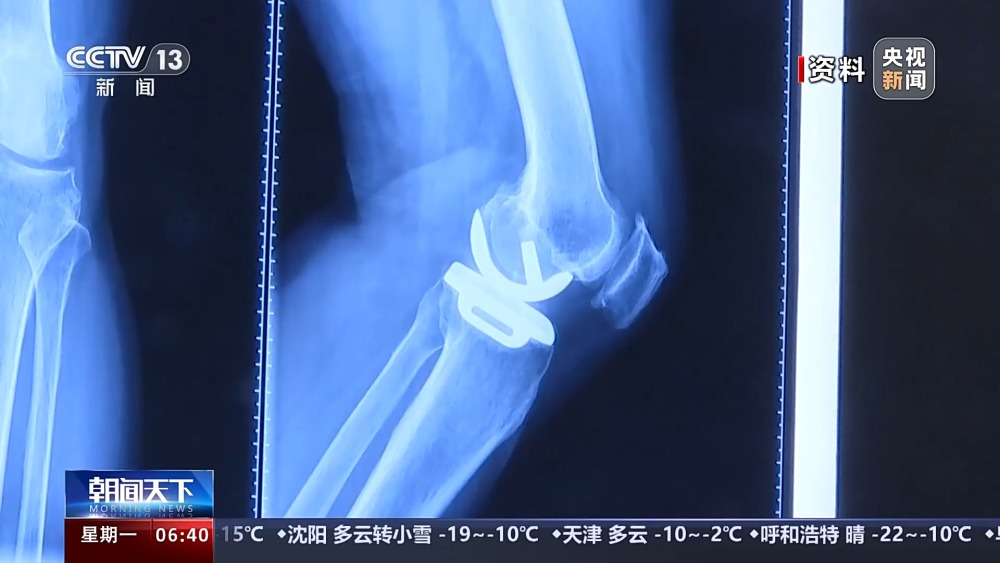

保膝手術(shù)主要包括截骨術(shù)和單髁置換術(shù),其中截骨術(shù)在解決患者疼痛癥狀的同時,阻止下肢異常應(yīng)力對膝關(guān)節(jié)的進一步損傷,膝關(guān)節(jié)內(nèi)所有軟骨韌帶、半月板都得到了保留。內(nèi)側(cè)單髁置換術(shù),使膝關(guān)節(jié)外側(cè)健康的軟骨和半月板得到了保留,膝關(guān)節(jié)內(nèi)外側(cè)的韌帶維持原有狀態(tài),患者康復(fù)后,擁有正常的膝關(guān)節(jié)功能。